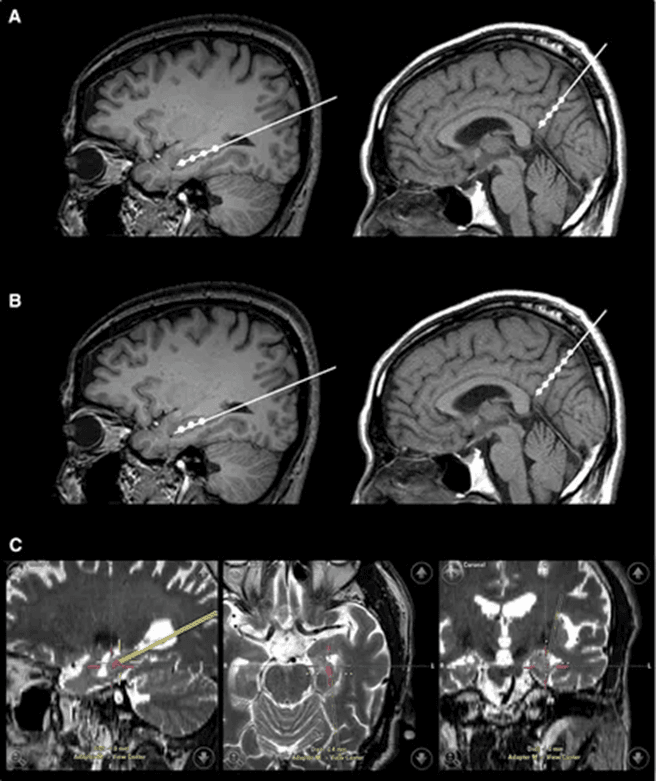

发表于《阿尔茨海默病与痴呆》(Alzheimer’s & Dementia)杂志的一项 1 期临床试验显示,研究团队对 9 例轻度至中度 AD 患者采用立体定向脑注射技术,将人间充质干细胞注入海马体与楔前叶(均为 AD 病理损伤关键脑区)。在长达 24 个月的随访中,所有患者均未出现发烧等严重不良事件,证实该注射方式具备可行性、安全性,且患者耐受性良好;